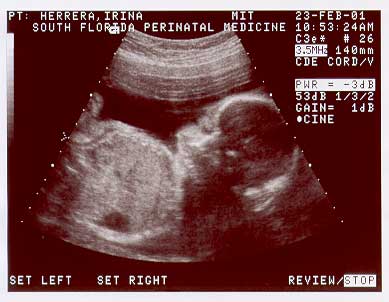

Welcome to the second page of Nicolas' u/s images taken on Feb. 23. 2001, at 25 wks.

BABY-2-25WK-2.jpg (19627 bytes)

Image sequence 5 of 6